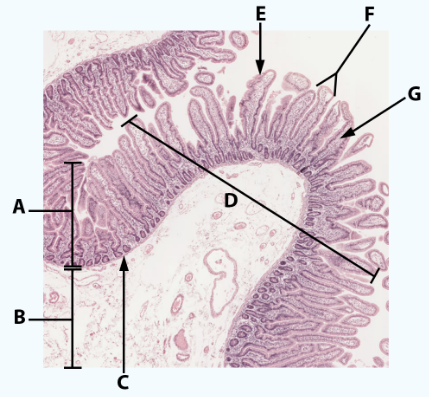

A

Mucosa: simple columnar epithelium with microvilli

B

Submucosa

C

muscularis mucosa

Area

Small intestine

E

simple columnar epithelium with goblet cells and microvilli

F

Villi

G

Lamina propria